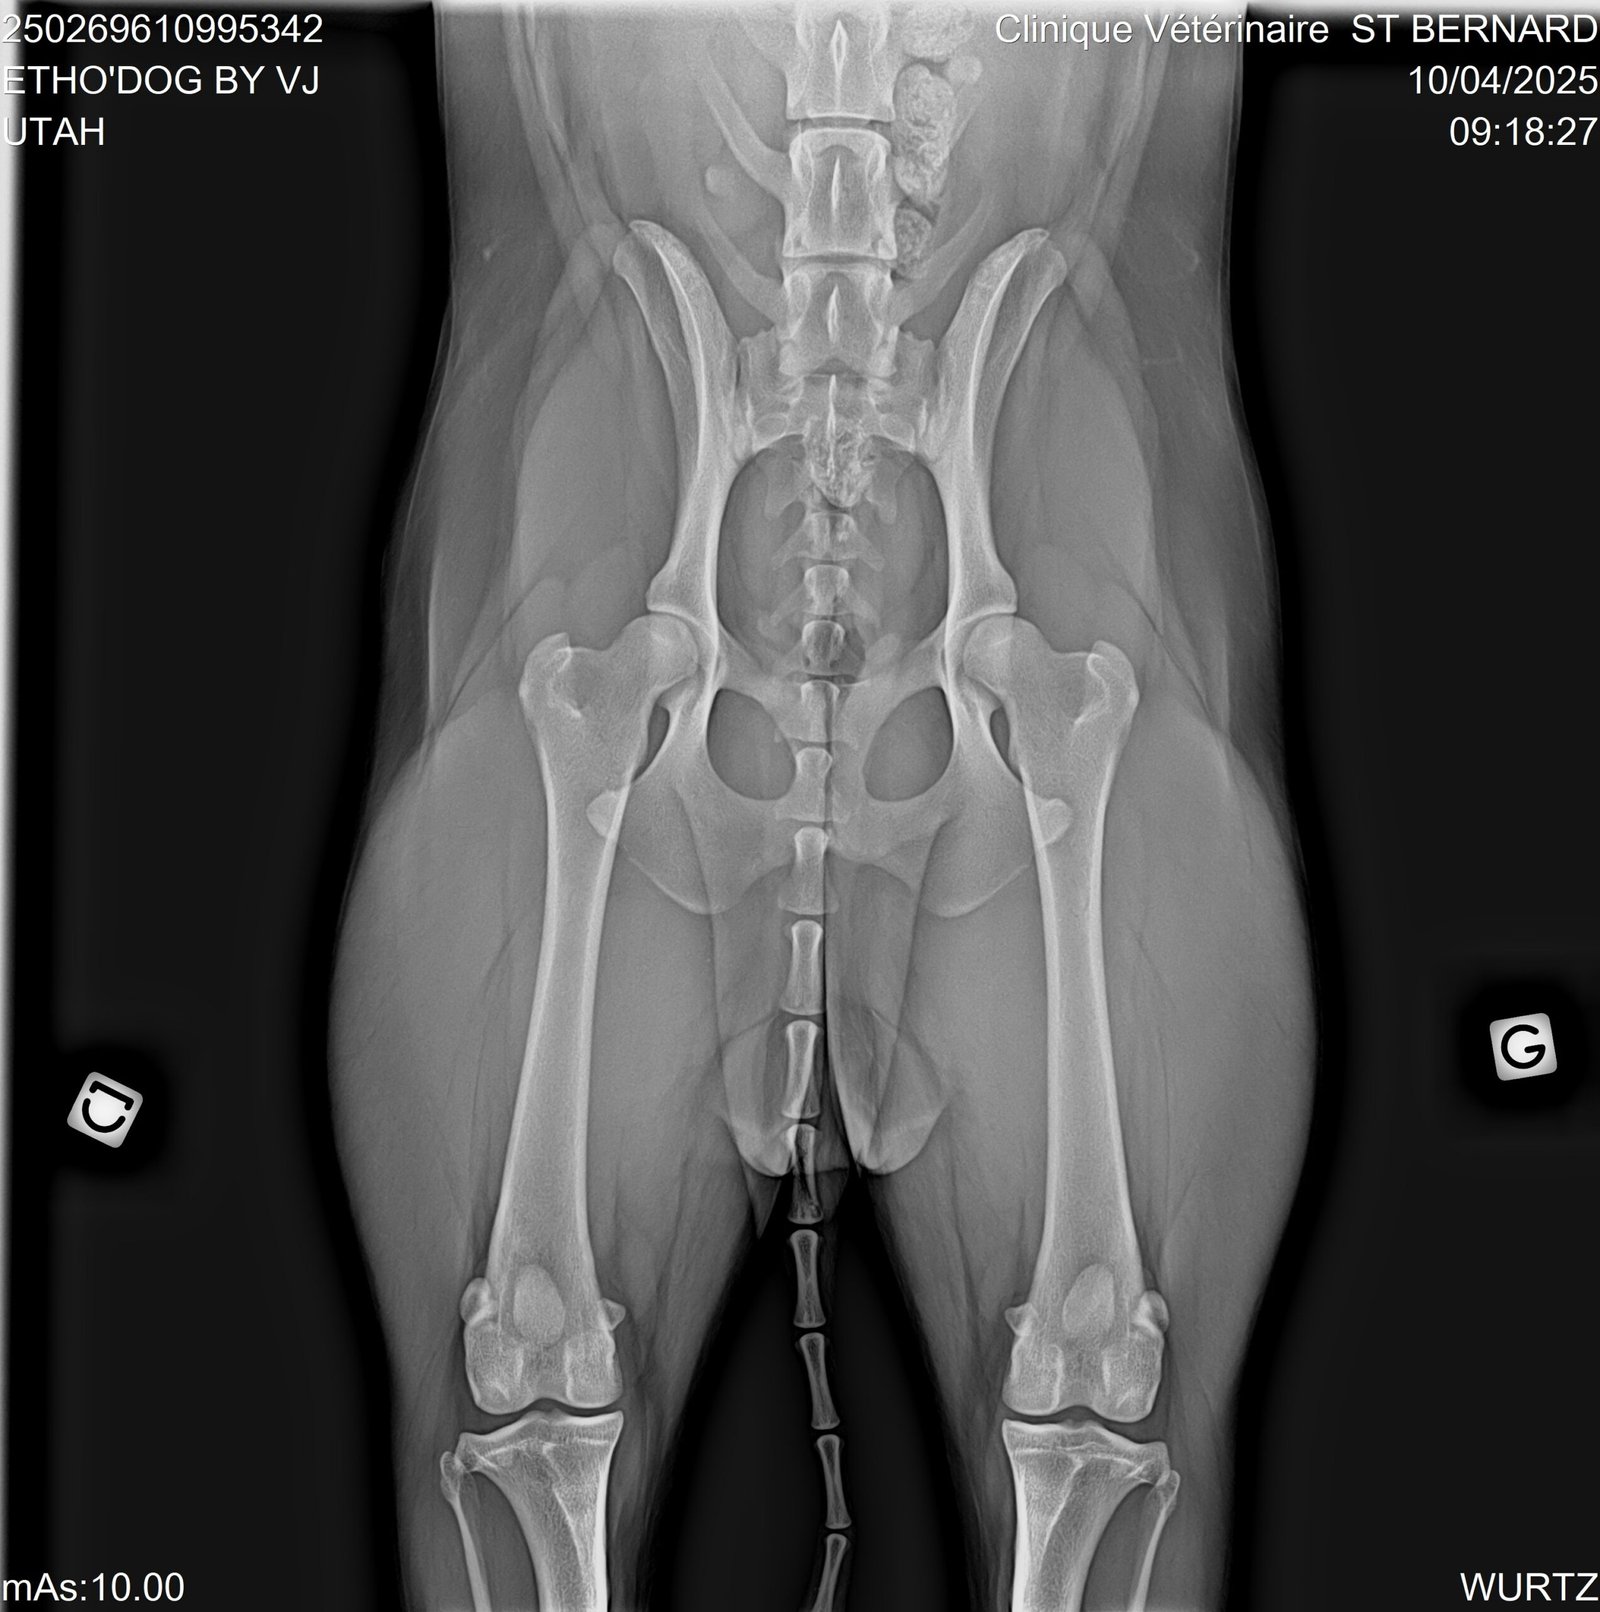

Radio des hanches de Utah